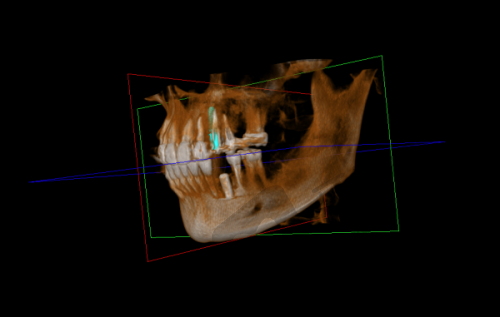

设备仪器:配备了精良的设备仪器,如CBCT机、全景机、超声洁治器、急救设备、烤瓷炉、根管填充器、激光设备、电动吸引器、口腔内窥镜、iTero口内扫描仪、高温高压消毒设备、热牙胶充填设备、超声骨刀等,为精细诊断和有效治疗提供有力保护。

厦门百姓口腔医院拥有一支技术熟练的医生团队,涵盖牙齿种植医生、牙齿矫正医生、牙齿修复医生、牙齿贴面医生及口内医生等。这些医生都具备丰富的从业经验,在各自的领域有着深厚的造诣。牙齿种植医生能够熟练运用各种种植技术,为患者提供稳定、持久的种植成效;牙齿矫正医生擅长根据患者的牙齿情况制定个性化的矫正方案,帮助患者拥有整齐美观的牙齿;牙齿修复医生在烤瓷牙、全瓷牙等修复方面技艺不错,修复后的牙齿与真牙无异;牙齿贴面医生能够精细地为患者进行牙齿贴面,改善牙齿外观;口内医生则在口腔疾病的诊断和治疗方面经验多,为患者提供专精的口内治疗服务。